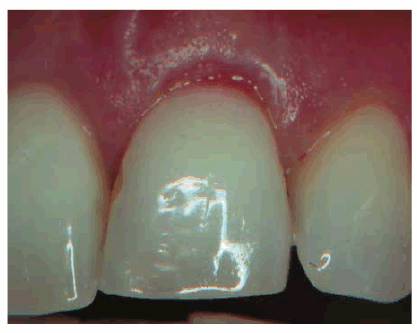

Transillumination via a fiber-optic light may be of great assistance in

detecting color shifts in a crown (Figures 19-1A, and 19-1B). A tooth with a pink or reddish

hue would more than likely indicate internal hemorrhage from a recent injury (Figure 19-2), a dental procedure (Figure 19-3), or gingival tissue hyperplasia

Figure 19-1A: Transillumination of a maxillary left central incisor with a necrotic pulp.

Figure 19-1B: Transillumination of the adjacent tooth with a vital pulp. Because there is active blood flow through the live pulp tissue, the tooth appears brighter to the fiber-optic light than the adjacent tooth with a necrotic pulp.